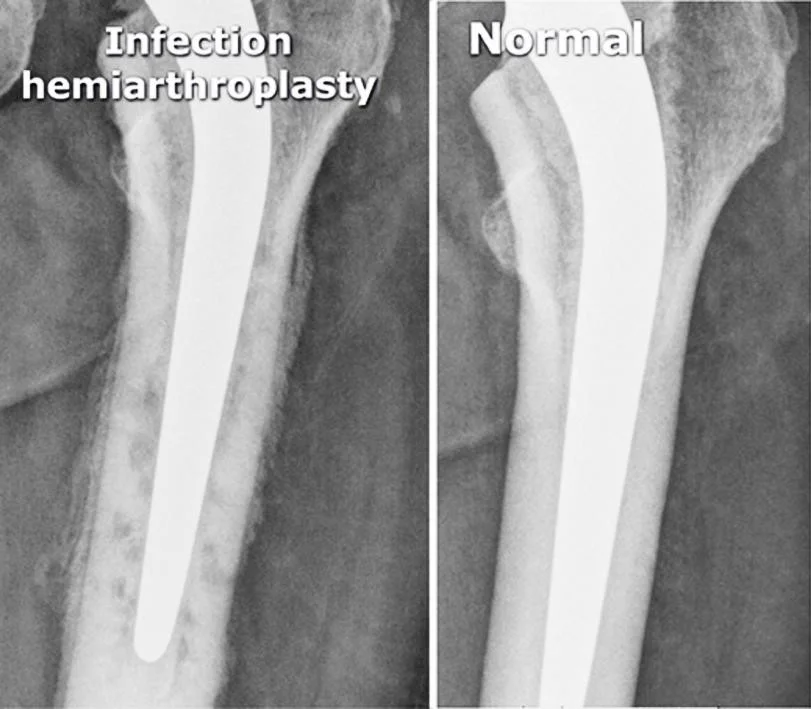

Arthroplasty

- Total Hip Arthroplasty (THA)

- Hemiarthroplasty (HAP)

Infected Arthroplasty

- Pain after arthroplasty

- Mild fever

Infection hemiarthroplasty

- vague periprosthetic bone resorption

- periosteal reaction

- cement

Normal

- hemi-arthroplasty